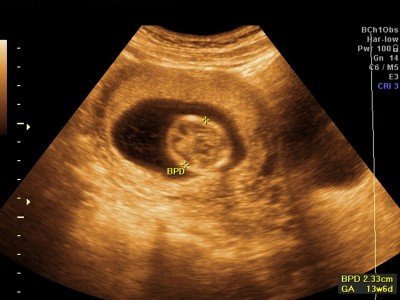

BPD | biparietal diameter | příčný průměr hlavy (vzdálenost temenních kostí) |

GA | gestational age | gestační stáří (stáří těhotenství) |